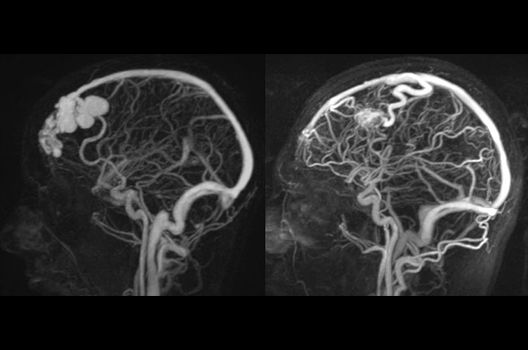

- Arterielle und venöse Angio-MRT

Die Magnetresonanztomographie (MRT) ist ein Verfahren, bei dem durch magnetische Kräfte Bilder des Körperinneren angefertigt werden. In der Neuroradiologie können manchmal kleinste Veränderungen schwere Folgen haben; daher forschen wir an der Entwicklung hochauflösender MRT-Sequenzen, mit denen diese Prozesse und auch einzelne Nervenfaserbahnen sichtbar gemacht werden können. Darüber hinaus sind bei vielen Erkrankungen des Gehirns die Blutgefäße betroffen. Daher arbeiten wir an der Neu- und Weiterentwicklung von MRT-Sequenzen zur Darstellung der Blutgefäße und zur Blutflussanalyse (sog. „Angio-MRT“). Einen besonderen Forschungsschwerpunkt unserer Klinik stellen die MR-Protonenspektroskopie und die funktionelle MRT dar, mit denen die Analyse einzelner chemischer Substanzen im Hirngewebe oder die Darstellung ausgewählter Hirnfunktionen möglich ist.